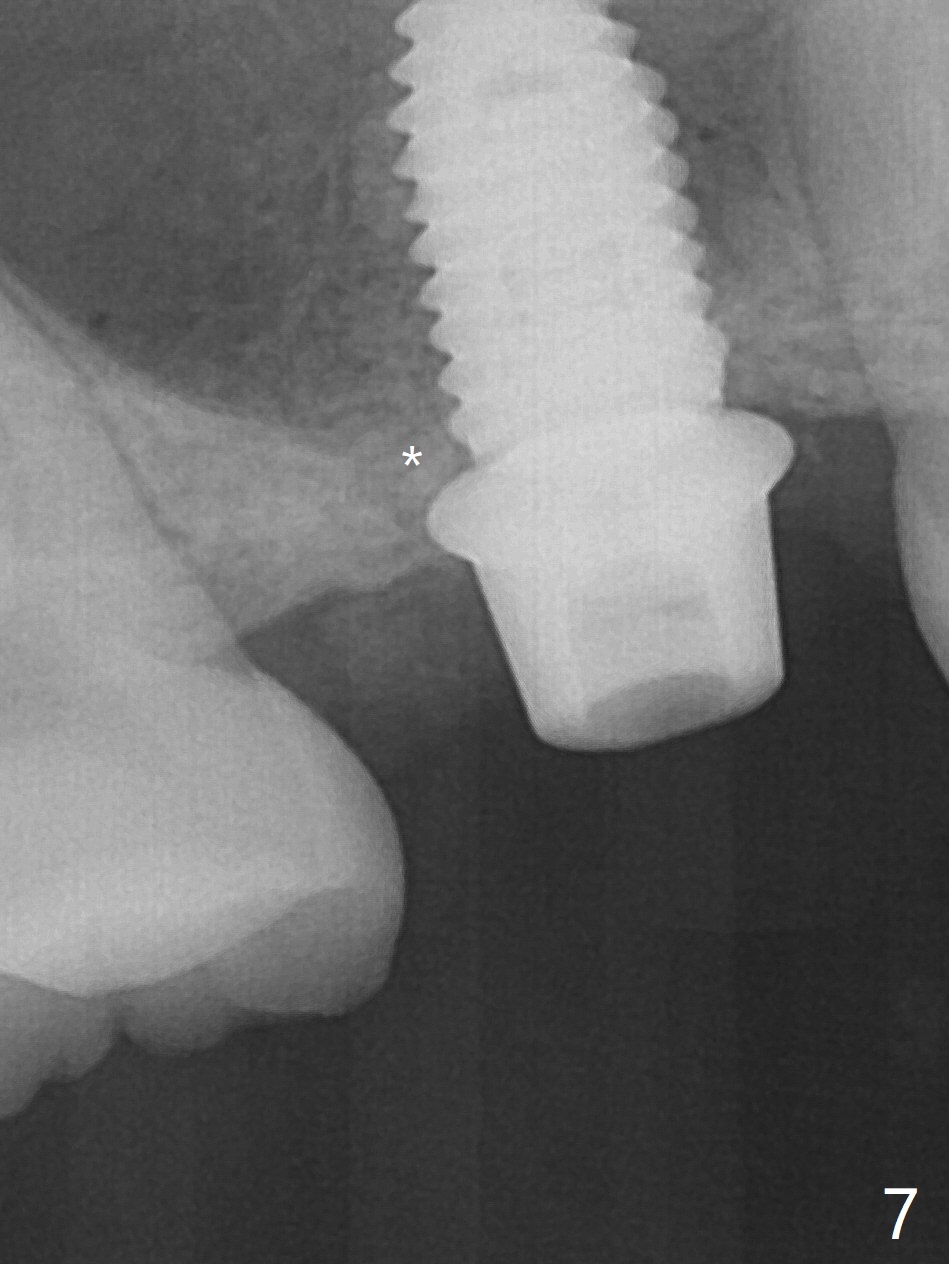

When the residual roots of the tooth #3 are removed, there is a gingival band over the septum (Fig.1 S). Osteotomy (Fig.2 yellow circle) would tear it off. To save the soft tissue, the buccal attachment is severed (Fig.3 black line), the flap is rotated palatal (Fig.3 curved arrow) and sutured in place (Fig.5 S). After sinus floor breakdown (use of sinus drill for 16 mm) and use of membrane lifter/water, two pieces of PRF membrane are inserted. The membrane is so slippery that it is easy to enter the sinus for further sinus membrane lift and later allograft placement (Fig.4 *). A 4.5x10 mm dummy implant is placed with high torque after 4x7.3 mm drill with 3 mm stopper so that 4.5x7.3 mm drill with 1 mm stopper is used before placement of a 5x8.5 mm final implant with ~ 35 Ncm (Fig.5-7). The patient reports anterior sinus wall tenderness with right nasal discharge a few days postop. The provisional has mobility without tenderness 1 week postop. It appears that the sinus membrane has been involved, which is quickly repaired probably by PRF. There is no pain when a 5.2x4(2) mm cemented abutment is torqued at 30-35 Ncm before impression (Fig.8). The surrounding soft tissue is healthy. When the permanent crown is delivered, the patient feels light pain when she bites hard. The discomfort persists 4 months post cementation (Fig.9). The crown/abutment is replaced with a healing abutment (Fig.10). There is no bone loss 4 months post healing abutment placement (14 months post implant placement, Fig.11). Upper Molar Immediate Implant, Prevent Molar Periimplantitis (Protocols, Table), Trajectory II, 31 Flap Not Transferred Xin Wei, DDS, PhD, MS 1st edition 07/26/2019, last revision 10/05/2020